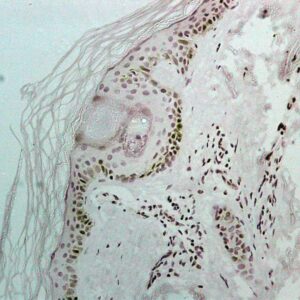

BioGenex has pioneered the development of miRNA research and diagnostics tools with leading-edge products. Currently, we offer over 240 ready-to-use (RTU) Super Sensitive™ Nucleic Acid (SSNA) miRNA ISH probes for accurate and early tumor diagnosis. These probes are sensitive enough to detect low-abundant miRNA(s) that are often required to identify biomarkers. They have a high melting temperature enabling stringent washes to remove non-specific binding. BioGenex miRNA probes are dual-end labeled with an anti-fluorophore to amplify the signal and yield clean and intense staining.